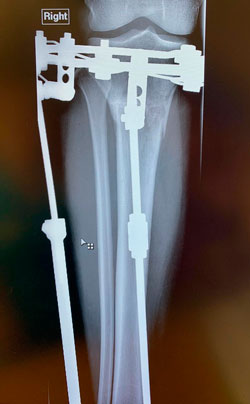

Рентген перед снятием аппаратов 85 дней

Дата операции - 11.10.2019.

Дата снятия аппаратов 14.01.2020

Срок сращения 93 дня.